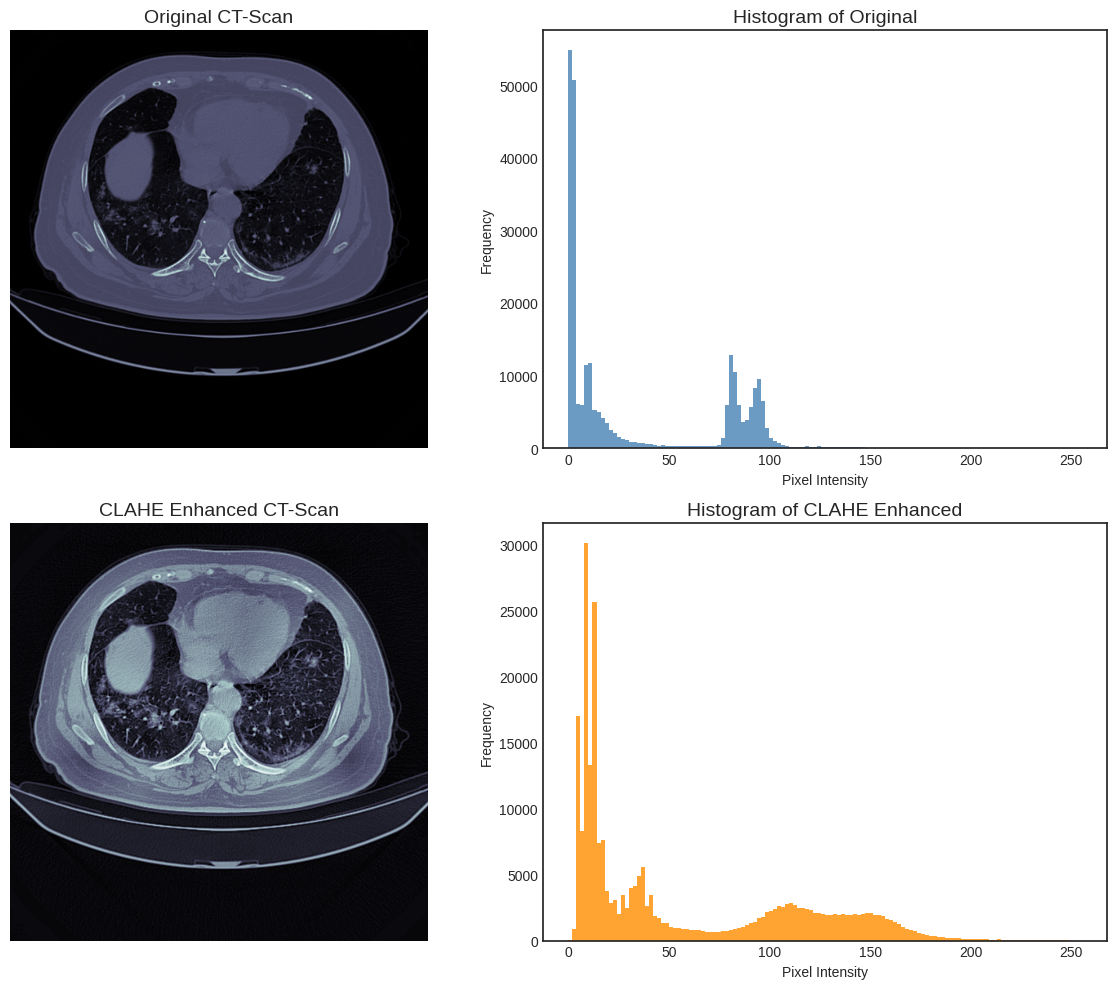

To prepare the images for classification, two key enhancement and extraction steps are applied. The first is Contrast Limited Adaptive Histogram Equalization (CLAHE). This technique improves the local contrast of the CT images, which is essential for highlighting subtle pathological features like ground-glass opacities. Unlike standard histogram equalization, CLAHE avoids over-amplifying noise in homogeneous regions by operating on small, distinct tile grids and limiting the contrast enhancement.

Figure 2 illustrates the effect of CLAHE on CT scans. The original CT image (top left) and its corresponding histogram (top right) show that most pixel intensities are clustered in narrow low-value ranges, limiting contrast between anatomical structures. After applying CLAHE (bottom left), the enhanced image exhibits improved visibility of lung details, while the corresponding histogram (bottom right) demonstrates a more balanced distribution of pixel intensities across the full dynamic range. This redistribution enhances local contrast and highlights subtle structural variations that are less discernible in the original scan.

Refer to caption

Figure 2: Comparison of original and CLAHE-enhanced CT scans with corresponding histograms